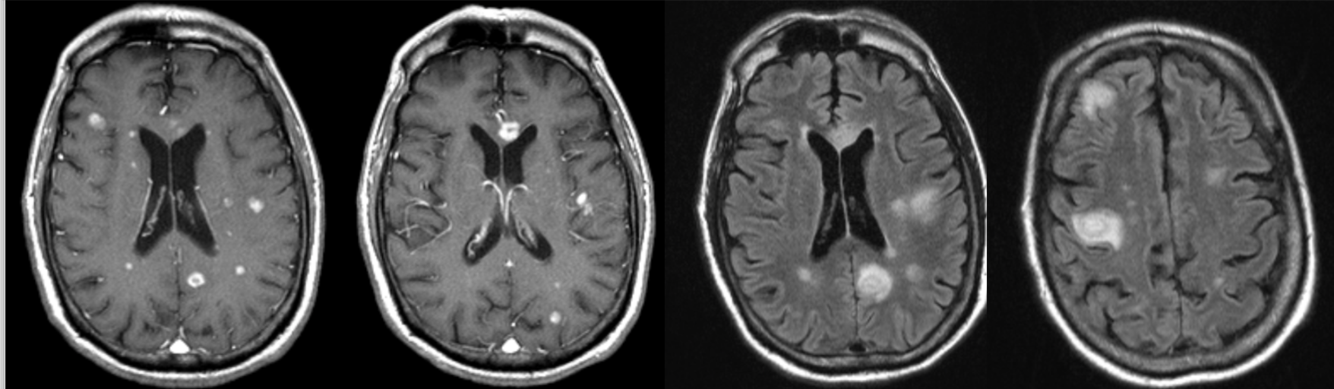

Encephalopathy and seizures in a patient with endocarditis from intravenous drug abuse.

Cerebral abscesses (early formation)

HIV patient with left-sided weakness.

Toxoplasmosis

Imaging